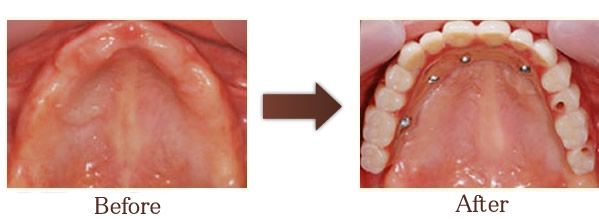

All-on-4の治療症例